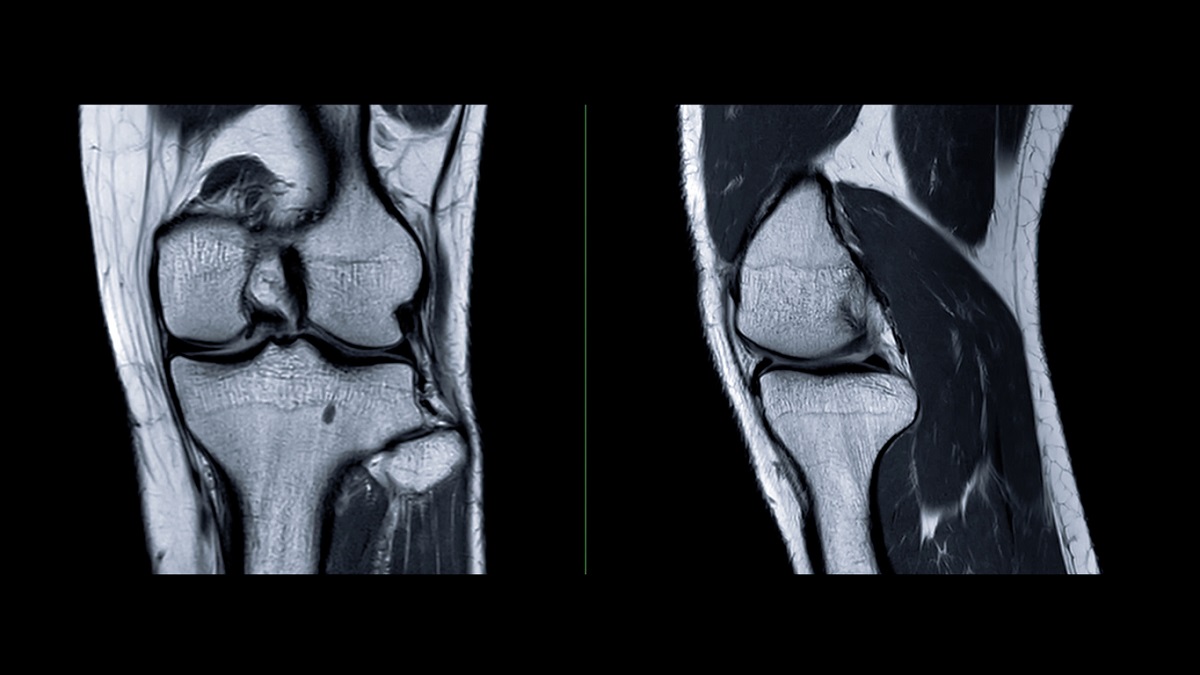

ΕΠΑΘΕΣ ΡΗΞΗ ΧΙΑΣΤΟΥ; ΟΡΘΟΠΕΔΙΚΟΣ ΧΕΙΡΟΥΡΓΟΣ ΕΞΗΓΕΙ ΤΙ ΓΙΝΕΤΑΙ ΤΩΡΑ

Η ρήξη χιαστού είναι ένας από τους πιο συχνούς τραυματισμούς στο γόνατο και μπορεί να αφορά άτομα κάθε ηλικίας, είτε ασχολούνται συστηματικά με τον αθλητισμό είτε όχι. Παρόλο που δεν πρόκειται για μια κατάσταση απειλητική για τη ζωή, αν δεν αντιμετωπιστεί σωστά μπορεί πραγματικά να πλήξει την καλή της ποιότητα, βάζοντας το άτομο σε μία κατάσταση κινητικής δυσκολίας, προκαλώντας αστάθεια, αυξάνοντας τον κίνδυνο να επεκταθεί ο τραυματισμός στους χόνδρους ή τους μηνίσκους, οδηγώντας σε βάθος χρόνου ακόμα και σε αρθρίτιδα.

– Η μορφή τραυματισμού του χιαστού μπορεί να διαφέρει από περίπτωση σε περίπτωση; Έχουμε ακούσει π.χ. για μερική ή ολική ρήξη.

Οι χιαστοί είναι δύο στο κάθε γόνατο: ο πρόσθιος και ο οπίσθιος. Στο 90% των περιπτώσεων τραυματίζεται ο πρόσθιος χιαστός.Ο οπίσθιος εξάλλου είναι και πολύ πιο παχύς και ισχυρός. Εμάς δεν μας απασχολεί αν είναι μερική ή ολική η ρήξη, αλλά αν ένας χιαστός επαρκεί λειτουργικά ή όχι, αν δηλαδή οι δεσμίδες που έχουν απομείνει δημιουργούν ένα σταθερό γόνατο. Μπορεί να έχεις μερική ρήξη χιαστού, αλλά να μην είσαι αθλήτρια, οπότε να δημιουργείται επαρκής σταθερότητα στο γόνατο. Το ζητούμενο, λοιπόν, δεν είναι απεικονιστικό αλλά αν το γόνατο επαρκεί για τις δραστηριότητες του ατόμου. Αυτό είναι κάτι που καταλαβαίνει και ο ίδιος ο ασθενής, αν το γόνατο «φεύγει», αν έχει αστάθεια. Βέβαια θα το επιβεβαιώσει και ο γιατρός.